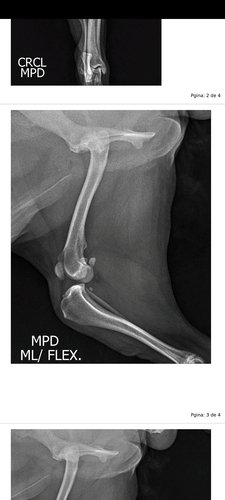

Infelizmente meu cachorro Pop rompeu o ligamento do joelho e precisa de uma cirurgia o mais rápido possível.